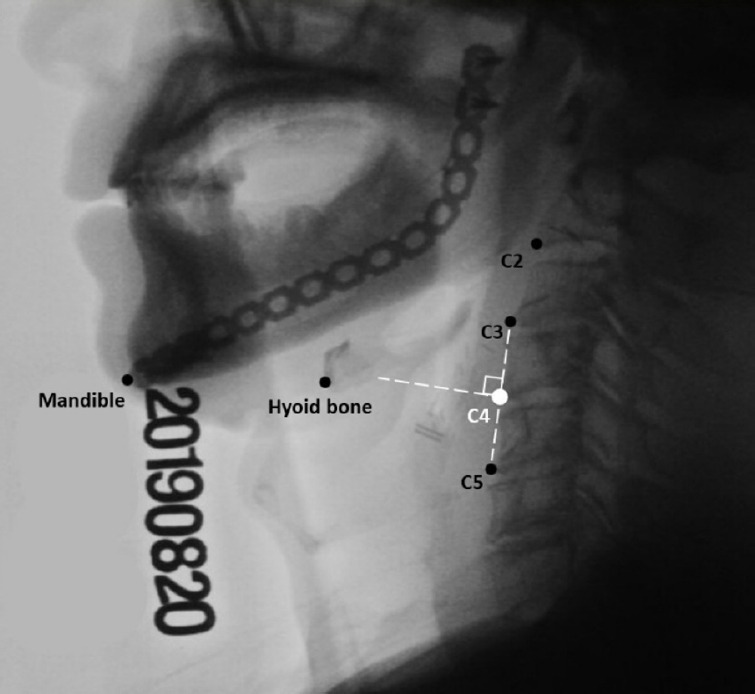

Objective: To investigate the temporal and kinematic parameters of hyoid bone excursion (HBE) in head and neck cancer (HNC) patients with and without aspiration.

Methods: Videofluoroscopic swallowing study images from 28 HNC patients were divided into aspiration and non-aspiration groups. The kinematic parameters of HBE, including displacement, instantaneous velocity, and instantaneous acceleration, as well as the timing of reaching maximal values in these parameters, were analyzed.